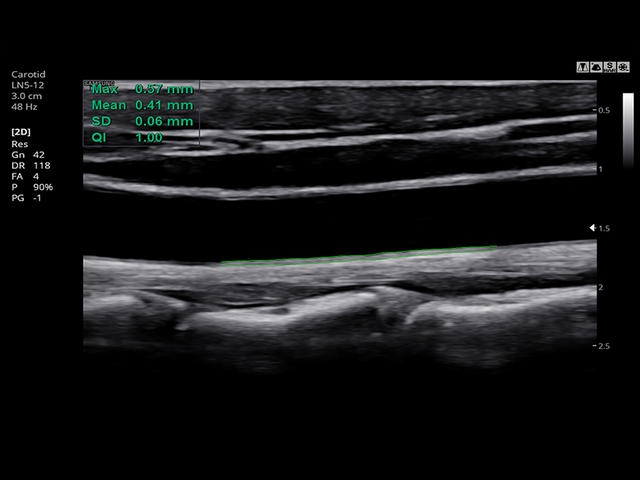

- Модуль Auto IMT - автоматическое вычисление комплекса интима-медиа общей сонной артерии (Intima Media Thickness). Данная оценка имеет большое значение для ранней диагностики атеросклероза и оценки риска развития инсульта и инфаркта миокарда.